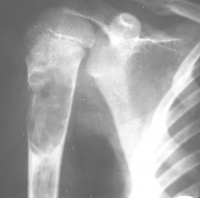

常发生于5到15岁的儿童,男性发病多于女性,比率约为2:1。病变部位多在长骨的干骺端。最常见部位为肱骨近端,其次为股骨近端。活动性(active相对具有侵袭性的)骨囊肿靠近骨骺区,随着儿童年龄增大,病灶会逐渐远离骨骺,成为非活动性(inactive)。在年龄超过17岁的患者,病变会在非长管骨发生,如跟骨、骨盆等。

有经验的骨肿瘤医生仅凭X线平片就可以作出骨囊肿的临床诊断。病变灶为边界清晰的液性低密度灶,四壁为薄层的硬化灶壳。病变灶略向近骨骺的干骺部位扩大。病灶非偏心性,也不破坏骨外壳,更不会突破骨质形成骨膜外反应骨,除非是在病理骨折后的愈合期。有时脱落的骨皮质成份落入囊腔中,X片显示被称为“落叶征”(FallenleaforFallenfragment)。当病灶发生在骨盆,CT扫描对病灶部位及囊肿形态的判断有价值。MRI可以明确囊内富含的液性成分。骨ECT扫描表现为外周薄的浓集而中央病灶冷区。

1.好发于4-20岁,多见于5-15岁儿童,少见于成人。好发于股骨颈、股骨上端和肱骨上端。随着年龄增长,囊肿逐渐向骨干方向移动。

3.X线摄片显示长骨干腄端或骨干部位有椭圆形溶骨破坏,边界清楚,其周围可见薄层硬化带,骨皮质可有轻度膨胀变薄。

3.X线摄片显示长骨干骺端有椭圆形密度均匀的透明阴影,病变局限,与

正常骨质间有明显界线,骨皮质膨胀变薄。

X线表现病损为界限清楚的射线透亮区,外有一薄层骨硬化边缘,由于囊肿膨胀性生长,造成骨皮质不规则变薄,X线片常呈假分叶状表现,尤多做囊肿在肱骨或股骨的干骺端向下扩展至骨干,向上扩展虽接近骨骺,但后者可被累及,病理性骨折很常见,囊肿可有骨嵴假象,病理检查见病损为单房的囊腔,其中充满清液,囊内衬以薄层纤维组织,骨折后腔内含血性液体并出现骨痂。

X线平片位于长骨干骺端,呈圆形、卵圆形或柱形,沿长骨纵轴发展,表现为轻度膨胀性生长,局部骨皮质变薄,边缘光整,无骨膜增生。合并病理骨折时,骨碎片向囊内移位,称“碎片陷落征”,有助于鉴别。

临床资料A组是待病理性骨折愈合后再治疗骨囊肿,共48例,年龄为6-43岁间;男39例,女9例。肱骨上端20例,肱骨中段6例,股骨上端9例其中(5例髋内翻),远端3例,股骨

主要通过X线片及病理来诊断。X线片示,多发生于长管状骨的干骺端,髓腔中心呈圆形或卵圆形的透光区,边缘清晰而硬化,长轴与骨的长轴一致,多呈中心性生长,无骨膜反应,可见一锐利透光线横过骨病损区。病理:囊内可有少量黄色或血性稀薄液体,囊肿壁内衬一薄层纤维组织,囊内可有骨嵴分隔。镜下见囊壁由成纤维细胞、多核细胞和胶原纤维构成。